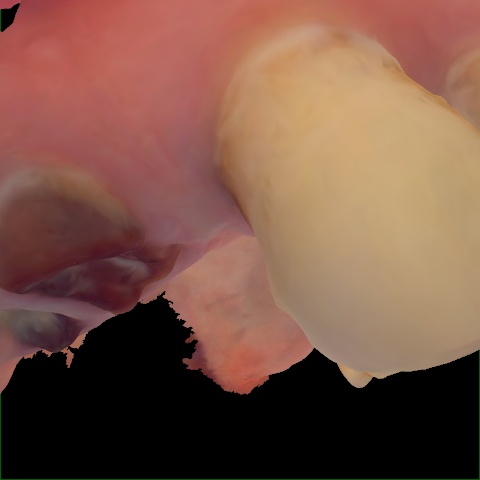

Annotated as "Good"